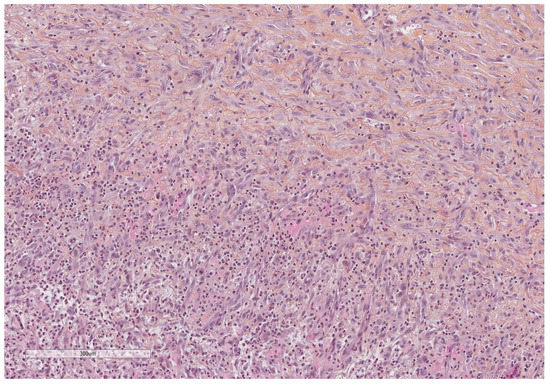

- Karpathiou, G.; Hathroubi, S.; Patoir, A.; Tiffet, O.; Casteillo, F.; Brun, C.; Forest, F.; Rahman, N.M.; Peoc’h, M.; Froudarakis, M.E. Non-specific pleuritis: Pathological patterns in benign pleuritis. Pathology 2019, 51, 405–411. [Google Scholar] [CrossRef] [PubMed]